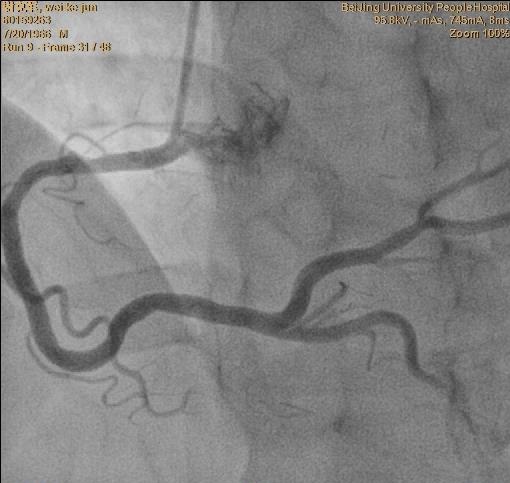

冠脉造影提示:双支病变。 见下图:

•术后一周复查造影,了解LIMA桥的状况,同时行RCA 和D的介入治疗。见下图: